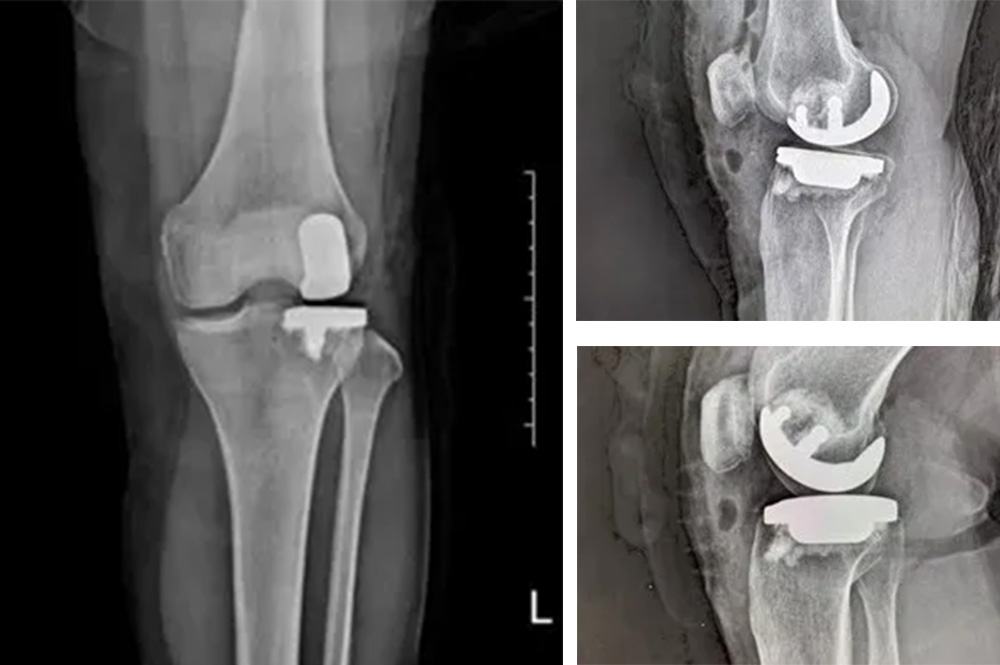

我院骨科主任羅醫(yī)生介紹,膝關(guān)節(jié)分為內(nèi)側(cè)、外側(cè)和髕股三個間室。鮑奶奶的問題主要集中在膝關(guān)節(jié)外側(cè)間室,而內(nèi)側(cè)和髕股關(guān)節(jié)相對完好。

“傳統(tǒng)全膝關(guān)節(jié)置換會切除所有關(guān)節(jié)面,而單髁置換只替換病變的部分,保留了健康的韌帶和軟骨,更符合‘精準(zhǔn)醫(yī)療’理念。”羅醫(yī)生說。

經(jīng)過詳細(xì)的體格檢查、影像學(xué)評估和三維重建,醫(yī)療團(tuán)隊確認(rèn)鮑奶奶的情況非常適合進(jìn)行膝外側(cè)單髁置換術(shù)。這種微創(chuàng)手術(shù)創(chuàng)傷小、恢復(fù)快,能夠最大程度保留膝關(guān)節(jié)的自然結(jié)構(gòu)和功能。

手術(shù)當(dāng)天,骨科團(tuán)隊采用微創(chuàng)切口,僅約8厘米,遠(yuǎn)小于傳統(tǒng)全膝關(guān)節(jié)置換手術(shù)切口。術(shù)中精準(zhǔn)定位,僅置換病變的膝關(guān)節(jié)外側(cè)間室。

手術(shù)使用了最新的單髁假體系統(tǒng),這種假體設(shè)計更符合人體工程學(xué),能夠更好地恢復(fù)膝關(guān)節(jié)的自然運(yùn)動軌跡。